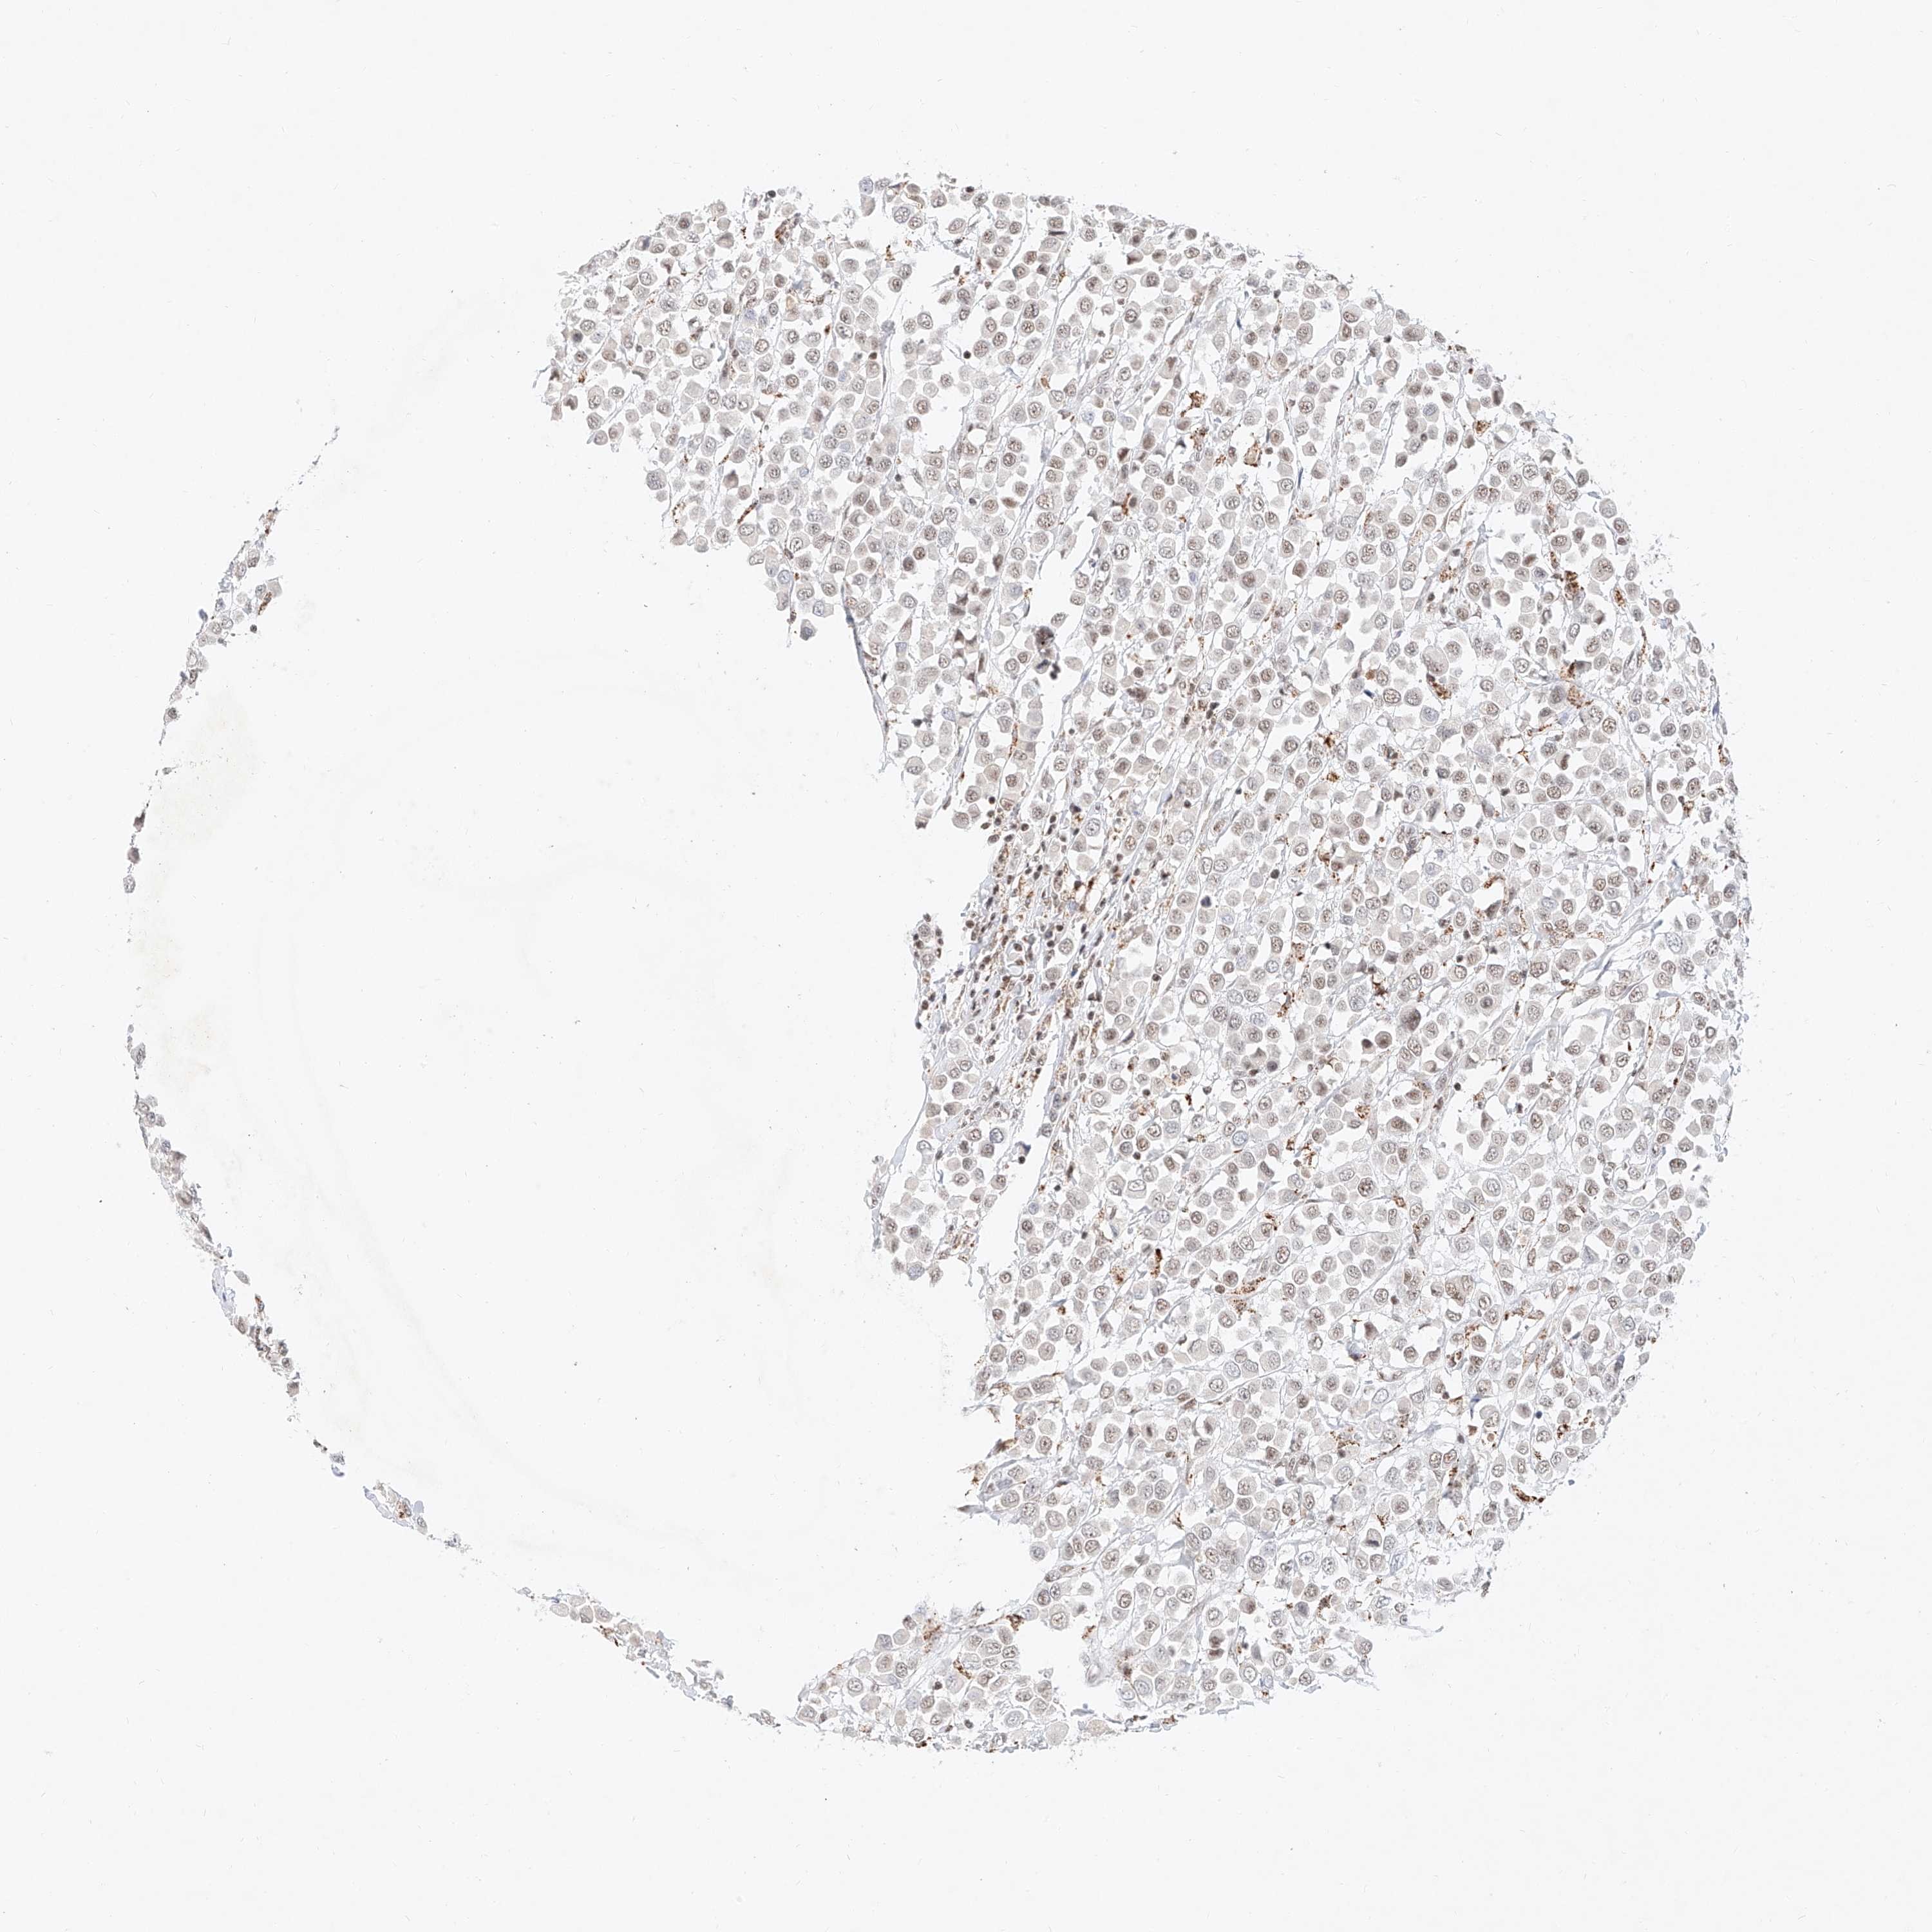

CANCER BREAST CANCER Show tissue menu

BRCA TCGA BRCA VALIDATION PROTEIN EXPRESSION

Breast cancer

Human cancer

NRF1 is not prognostic in Breast Invasive Carcinoma (TCGA)